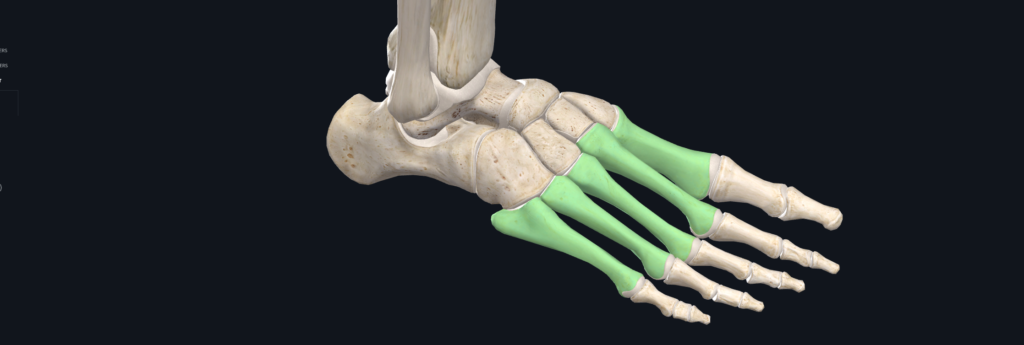

人類足部的蹠骨相當於於手的掌骨,手的掌骨用來抓握,

腳的蹠骨用於承受地面的彎曲力矩與應力。